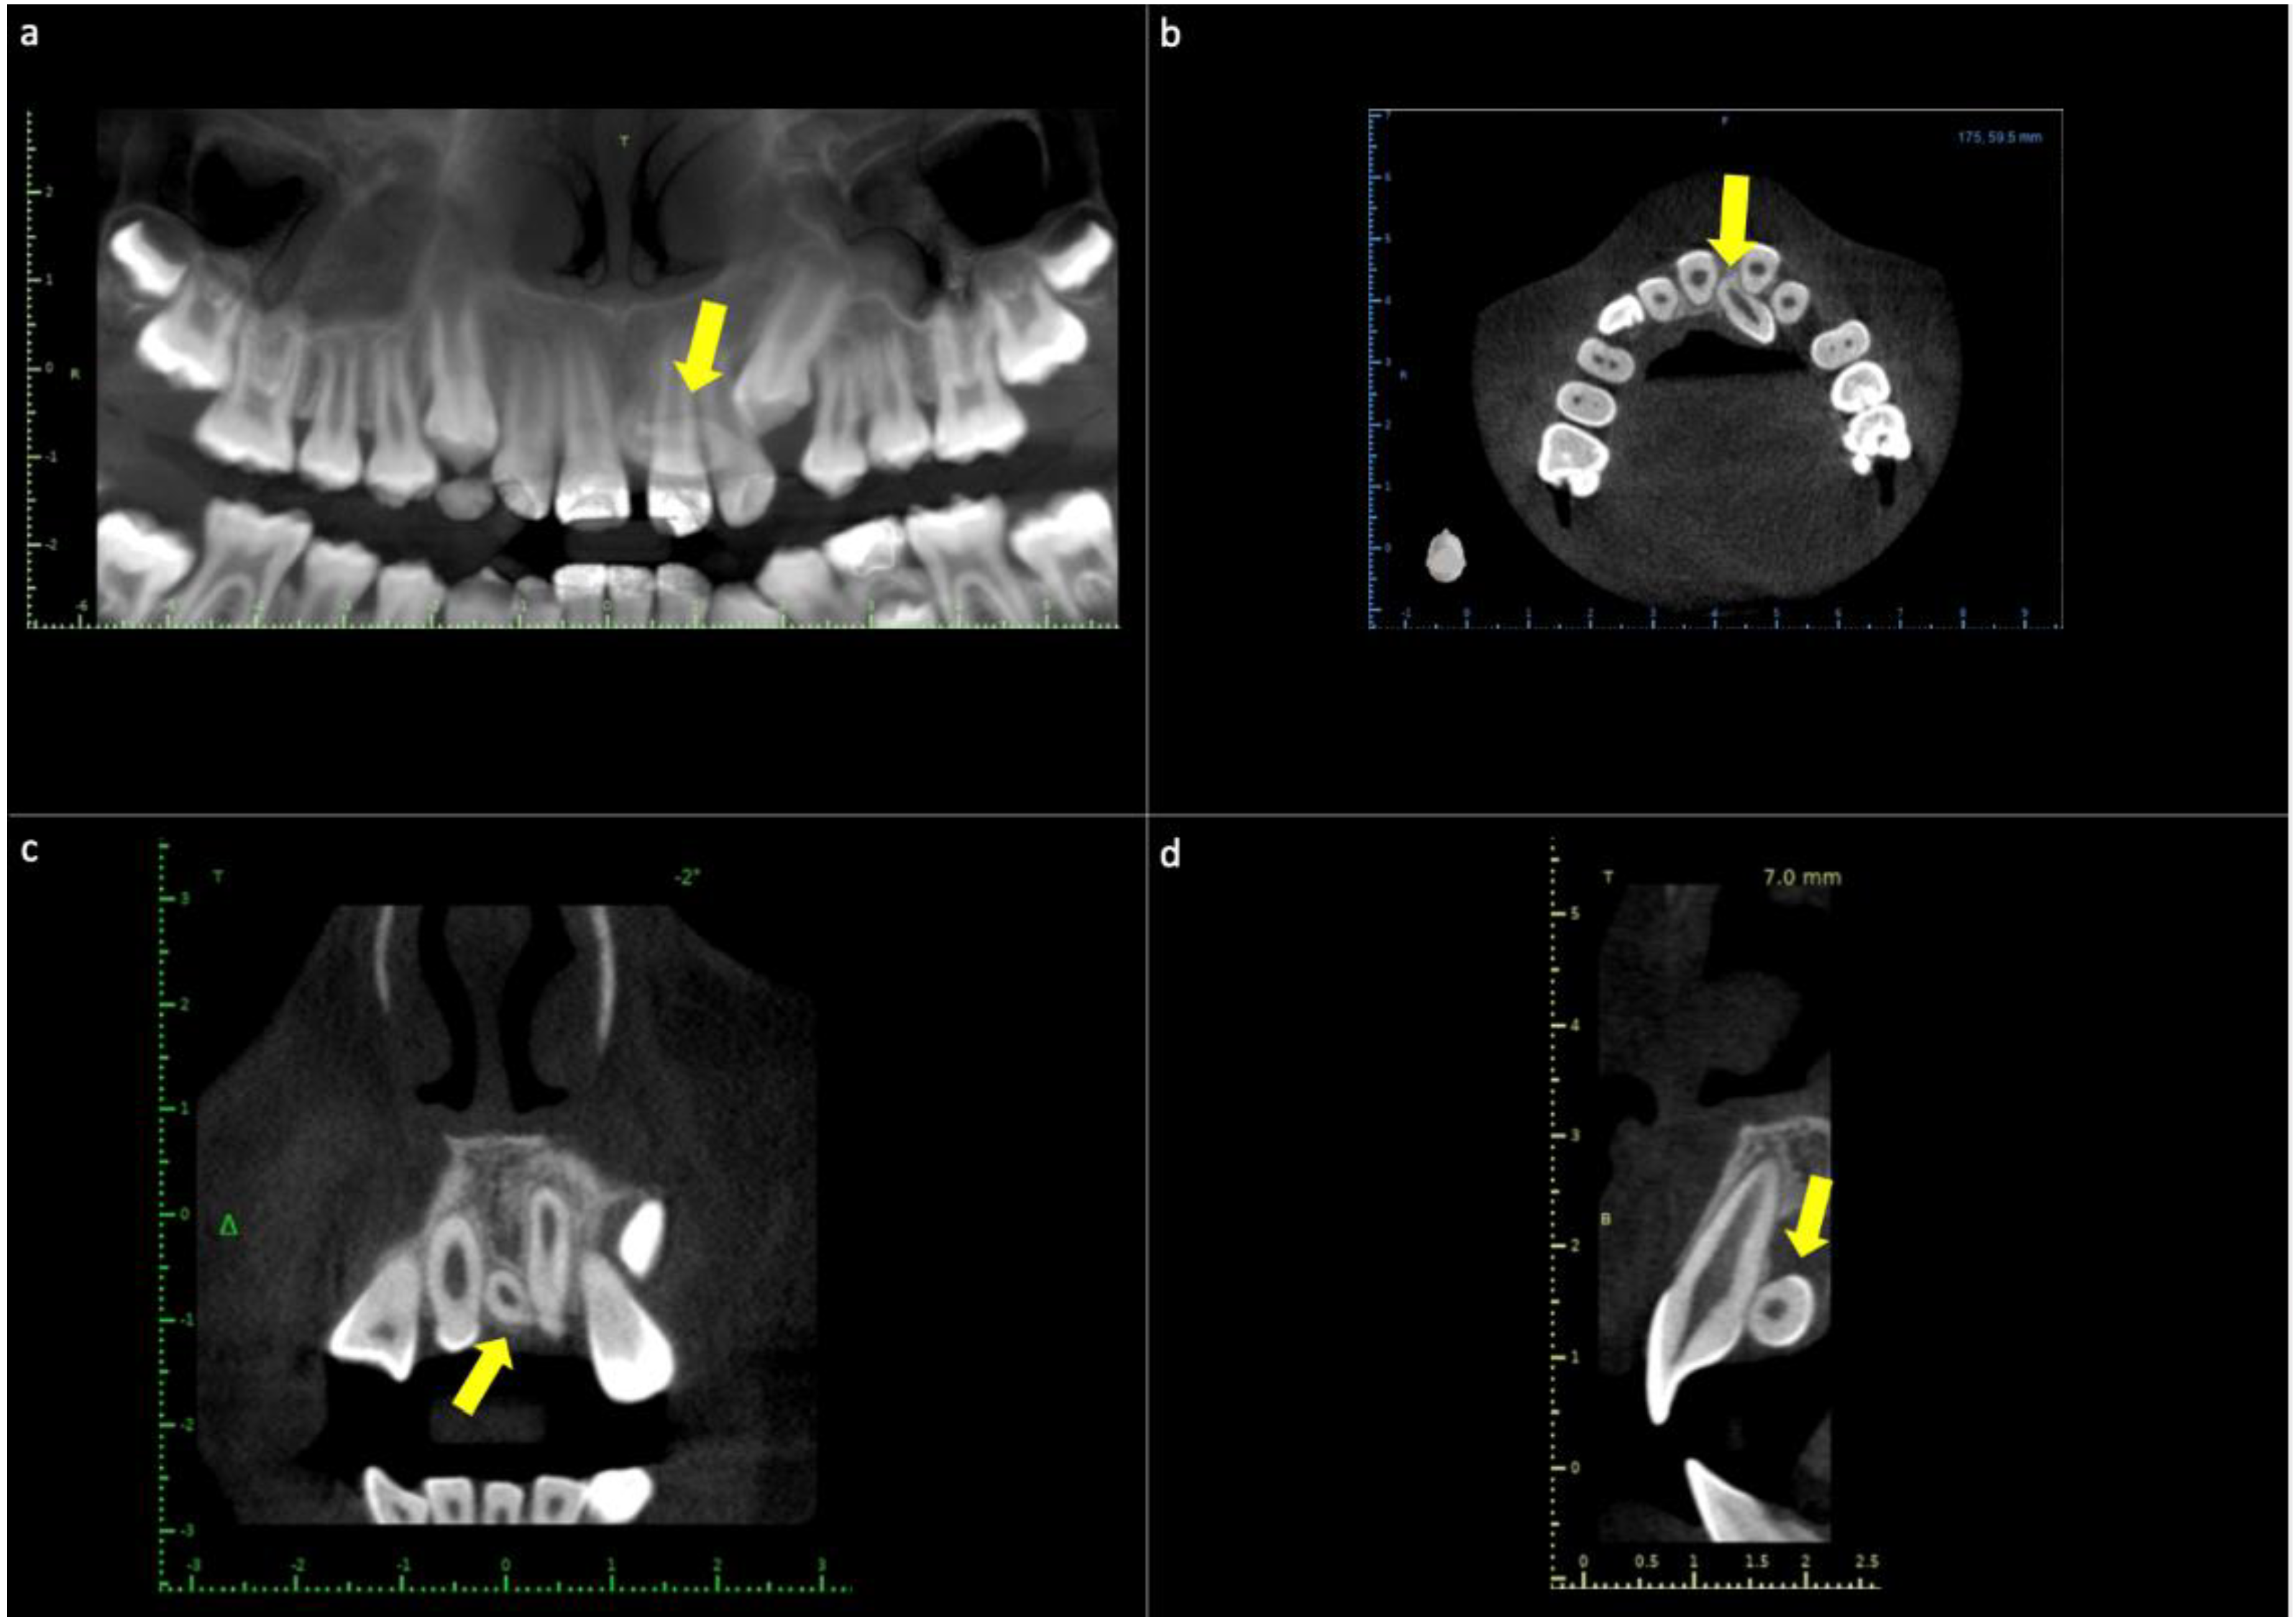

Mesioden supernumerary extraction tooth upper incisors CBCT kazemi oral Dental Code For Extraction Of Mesiodens A mesiodens is an extra tooth that’s located behind or between your two front teeth. D7140 extraction, erupted tooth or exposed root (elevation and/or forceps removal) includes removal of tooth structure, minor smoothing of. The client will need to setup service codes and ada codes to accommodate for the supernumerary tooth numbers that are required. Treatment options may include surgical. Dental Code For Extraction Of Mesiodens.